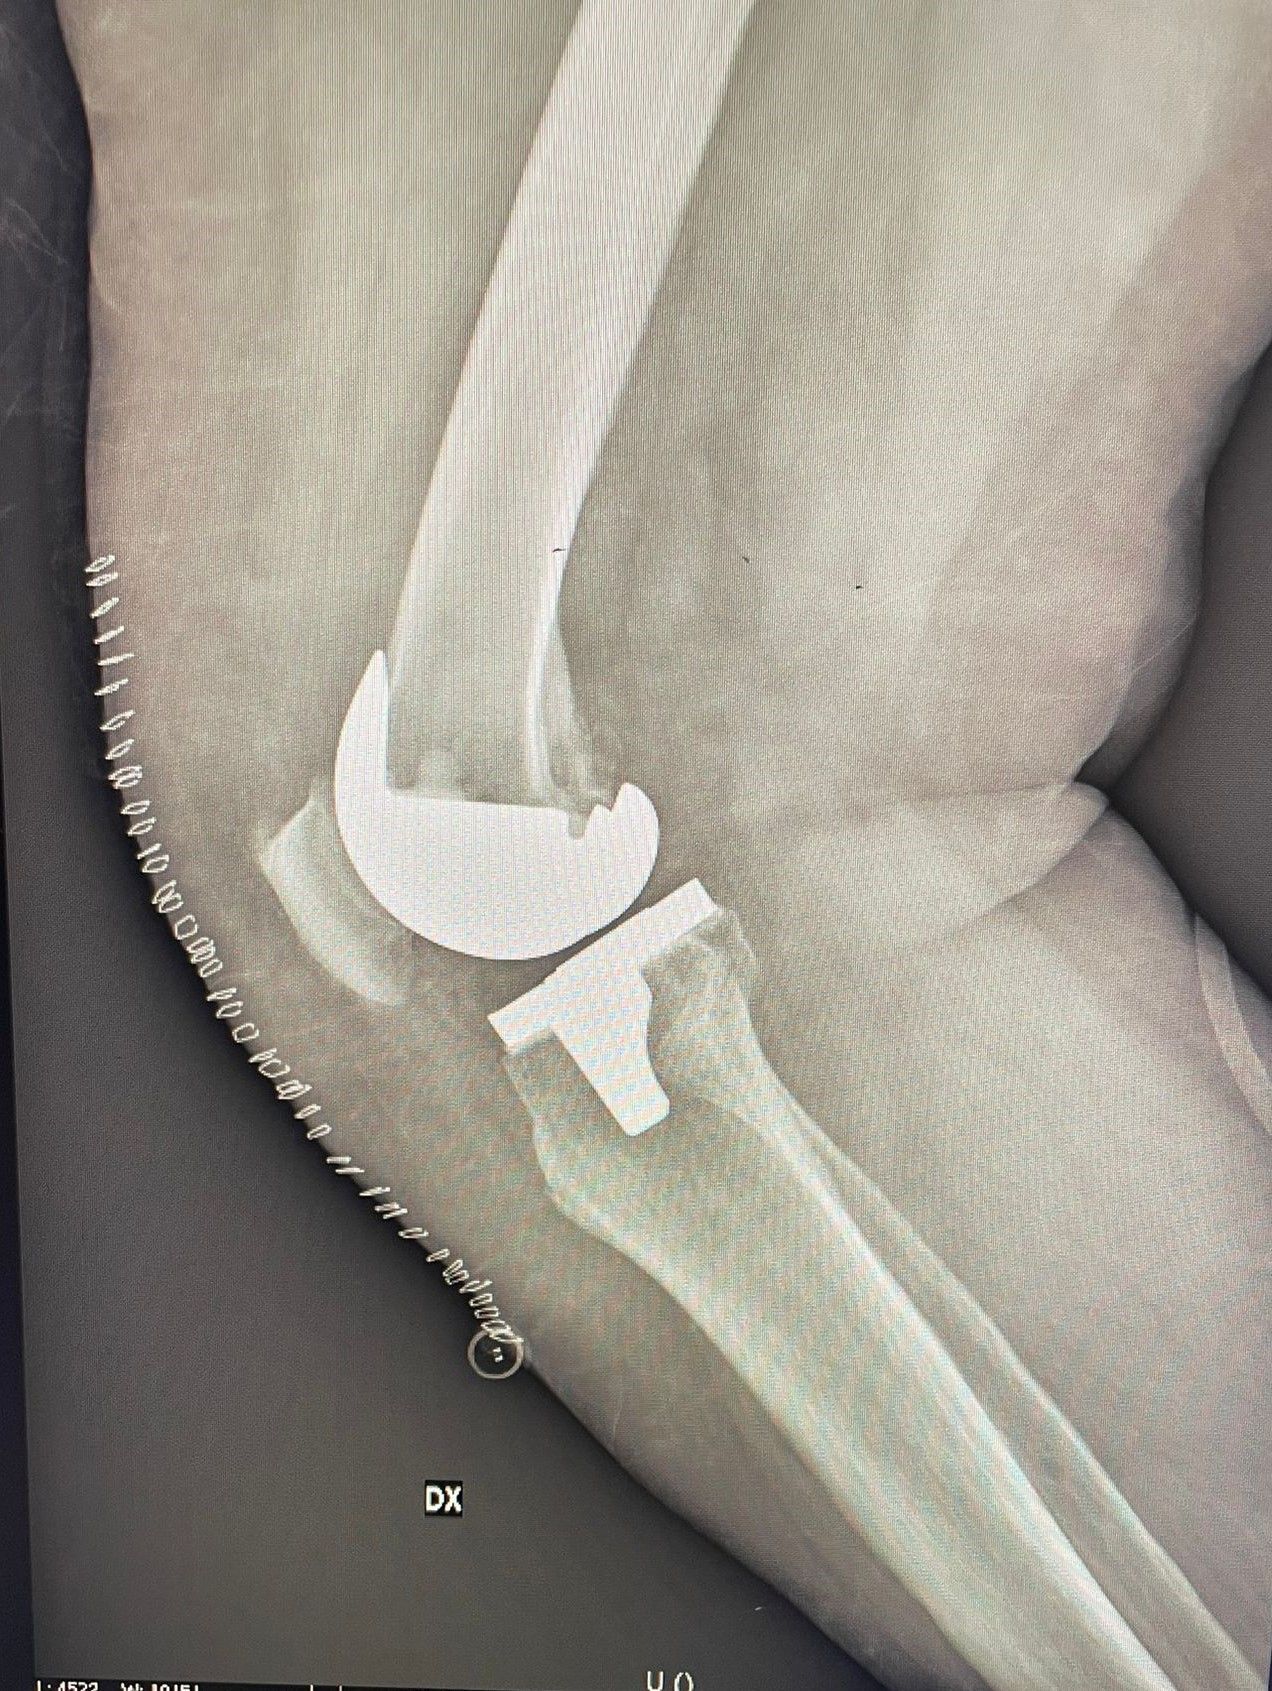

La protesi di ginocchio è costituita da una componente tibiale, una femorale, entrambe in lega di cromo-cobalto, ed un inserto in polietilene che aumenta la congruenza articolare e la stabilità dell’impianto protesico. In genere, le componenti protesiche si fissano all’osso con il cemento, oppure utilizzando degli impianti in tantalio, materiale che si osteointegra completamente entro 3 mesi, senza necessità di cementare.